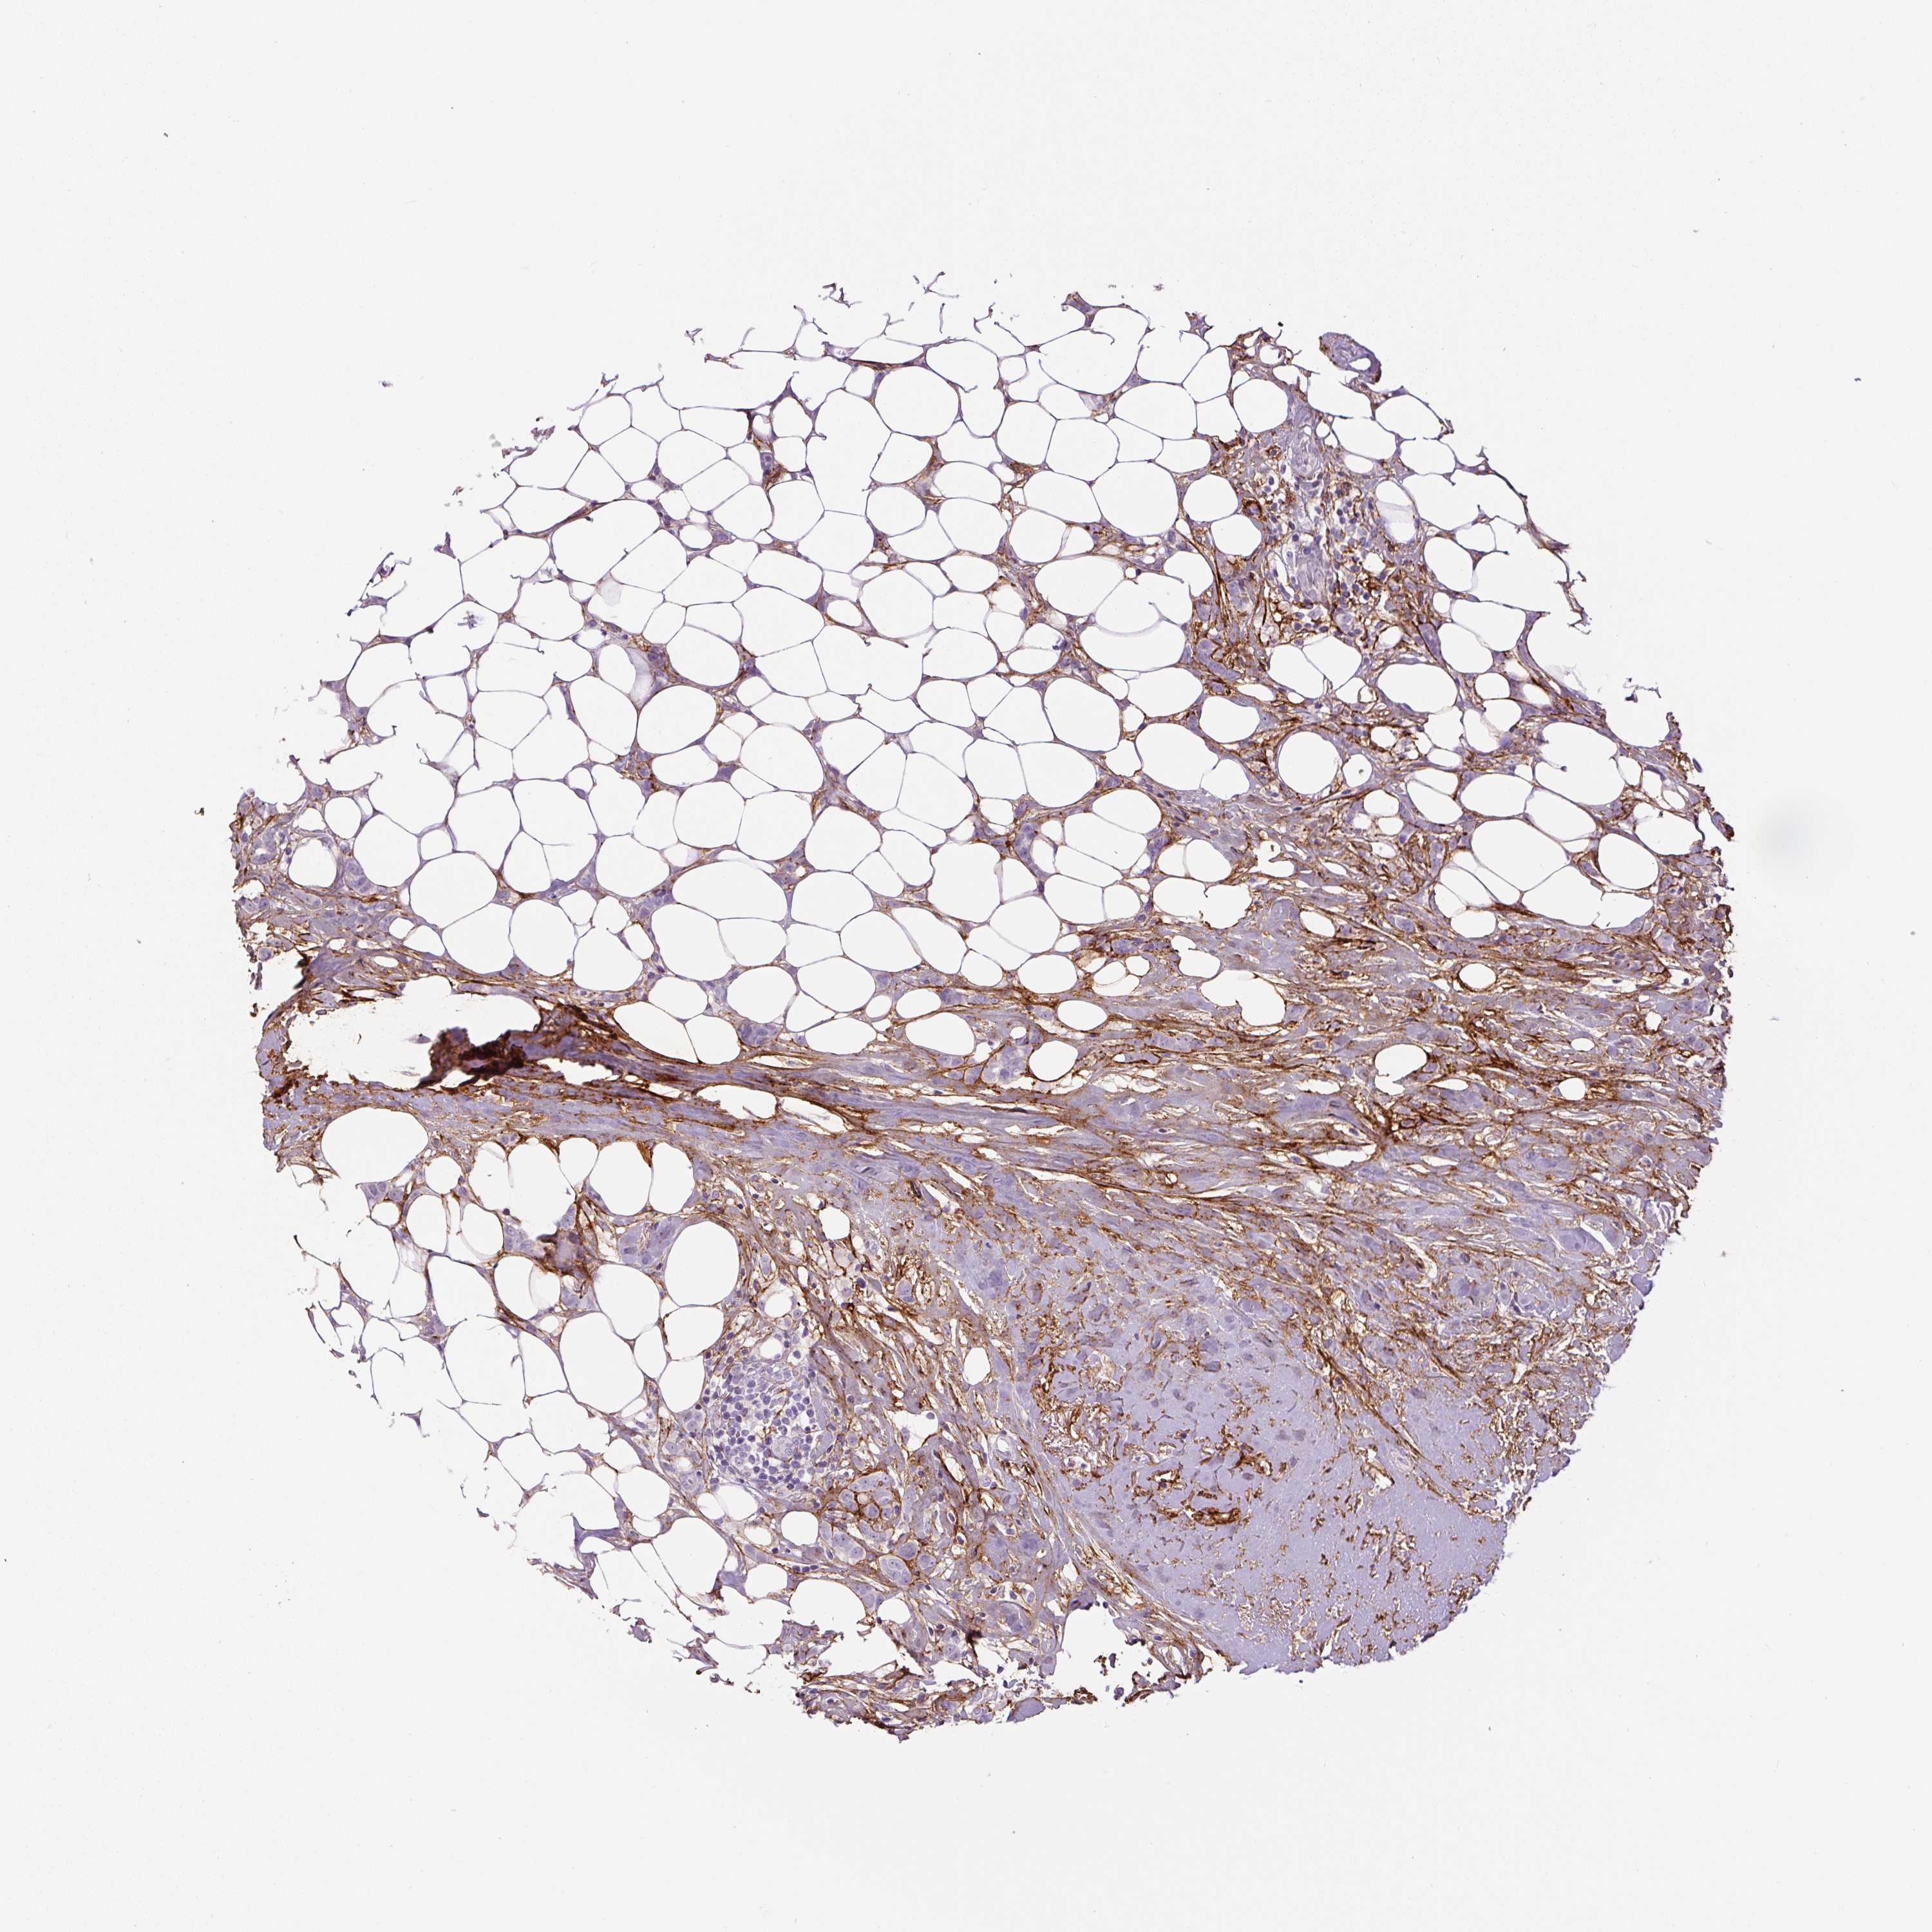

BRCA TCGA BRCA VALIDATION PROTEIN EXPRESSION

ANTIBODIES

AND

VALIDATION